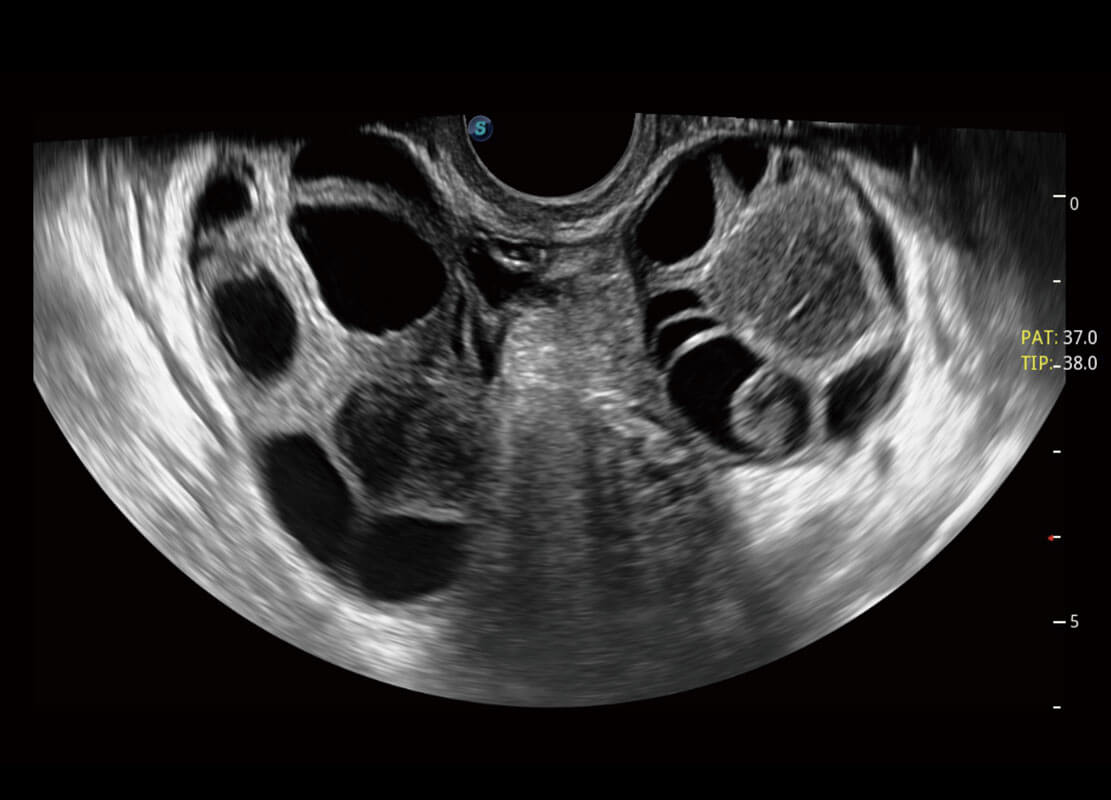

P60为盆底超声检查提供应用方案,多种腔内及腹部容积探头提供从二维、三维到四维的优异图像品质,实时快速三维容积数据获取,专业的测量工具包等人性化设计,为超声医生诊断提供有力保障。

能够简化盆底检查的操作流程,可在二维模式及三维成像模式下实现一键自动提取出标准切面、自动识别当前切面、自动测量,提升盆底检查的高效性,同时也能让青年医生快捷的获得准确的检查结果。